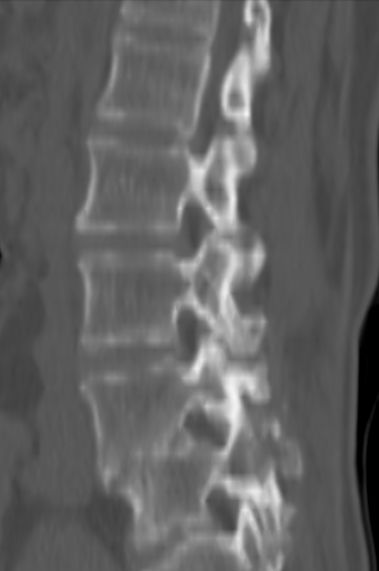

以下是引用余辉在2007-9-4 21:00:00的发言:[br]椎体棘突有点异常(像是被切割了),不知有否手术史,如椎体融合术等。单纯的退行性变可以出现椎间隙变窄,但同时一般会出现椎体上下缘的硬化增生,且椎体间完全融合的机率更小,本例椎体完全融合且椎体上下皮质缘破坏掉了,如果没有手术史,就应该考虑椎间盘炎性病变了,且椎体棘突及棘间韧带的变化也并不是不支持这个,多数小关节也融合了,且其形态也容易让人联想到如强脊炎及类风关等病变。[br][br][本贴已被 余辉 于 2007-9-4 21:03:55 修改过]

以下是引用chry3在2007-9-4 20:42:00的发言:[br]椎间盘病史?是什么样的病史,无双下肢放射痛,那就不是椎间盘突出了。是感染、什么性质的?[br]从图象看椎间隙消失,椎间盘组织未见,锥体滑脱是因为椎间盘溶解造成的[br]l4、5椎体骨质结构未见异常,l5上缘是l4的长期压迫所致[br]还是考虑椎间盘感染,结核。[br]